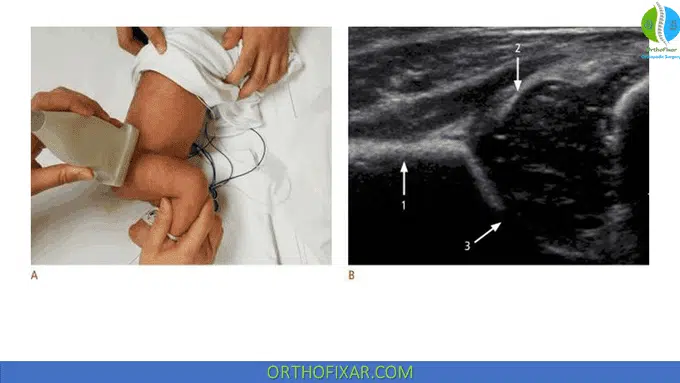

Graf method for infant hip ultrasound is a static morphologic evaluation of the infant hip. The infant is scanned in a lateral decubitus position with the examiner on the right side. The acetabulum appears on the right side of the image, the greater trochanter on the left side.

The hip joint is evaluated in a standard coronal plane with a linear array probe. Three key landmarks should be visualized in this plane:

- The inferior border of the ilium in the acetabular fossa.

- The central weight-bearing zone of the acetabular roof.

- The acetabular labrum.

The coronal view of the hip can be captured with the infant’s hip in either a standard neutral position, typically between 15° and 20° flexion, or a more flexed position. The ultrasound transducer is positioned in alignment with the coronal plane of the body. It is then moved back and forth from this foundational position to delineate the rounded configuration of the hip joint.

The image can be manipulated by slightly rotating the superior edge of the transducer posteriorly by an angle between 10° to 15° into an oblique coronal plane. This action gives the ilium a straight appearance. A standard plane of the hip is indicated if the sonogram illustrates a straight contour of the iliac wing, visibility of the triradiate cartilage, and a conspicuous acetabular labrum.

The American College of Radiology suggests performing a standard ultrasound examination in the transverse view, with the hip flexed at a 90° angle. In this perspective, the femoral shaft can be seen anteriorly, ending at the femoral head, which is resting on the ischium.

To detect a potentially dislocatable hip, the transducer is positioned in a posterolateral position while performing the Ortolani and Barlow maneuvers. If the connection between the posterior acetabulum and the femoral head shifts under gentle stress, it indicates instability in the hip.